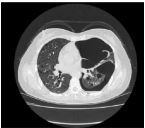

9.CC: 咳嗽 4 周,有痰